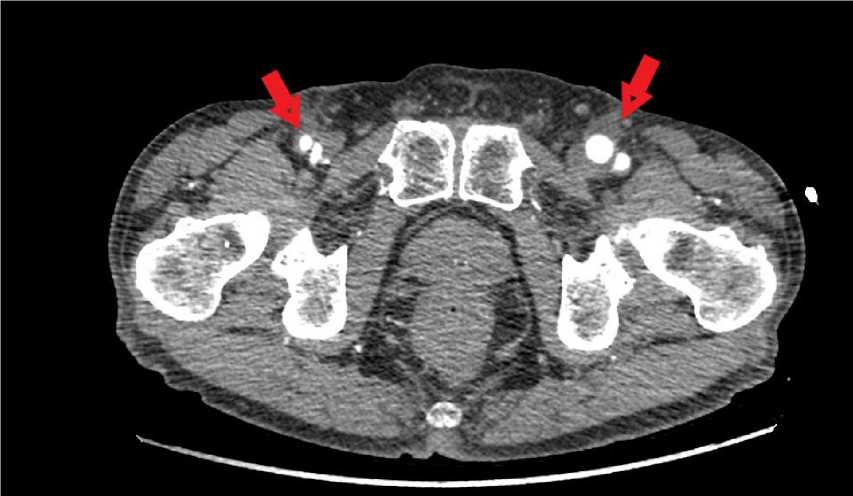

Материалы и методы. Исследование проведено на базе отделения сердечно-сосудистой хирургии ГКБ № 4 (г. Пермь). Критерием включения являлось наличие ограниченной инфекции дистального анастомоза после бифуркационного аорто-бедренного шунтирования; критериями исключения стали распространение инфекции на центральный анастомоз и в брюшную полость, обнаруженное при проведении компьютерной томографии (рис. 1), выполнение снятия инфицированной бранши протеза, отказ пациента от лечения по данной методике. Всего было отобрано 8 пациентов: 6 (75 %) мужчин было и 2 (25 %) женщины (табл. 1). Средний возраст составил 68±5 лет (от 59 до 72).

Рис. 1. Компьютерная томография с внутривенным контрастированием.

Стрелками отмечено скопление жидкости вокруг левой бранши бифуркационного протеза и бедренных артерий ниже анастомоза справа (пациент № 8)

Fig. 1. Computed tomography scans with intravenous contrast. Arrows indicate fluid accumulation around the left branch of the bifurcation prosthesis and the femoral arteries below the anastomosis on the right (patient No 8)